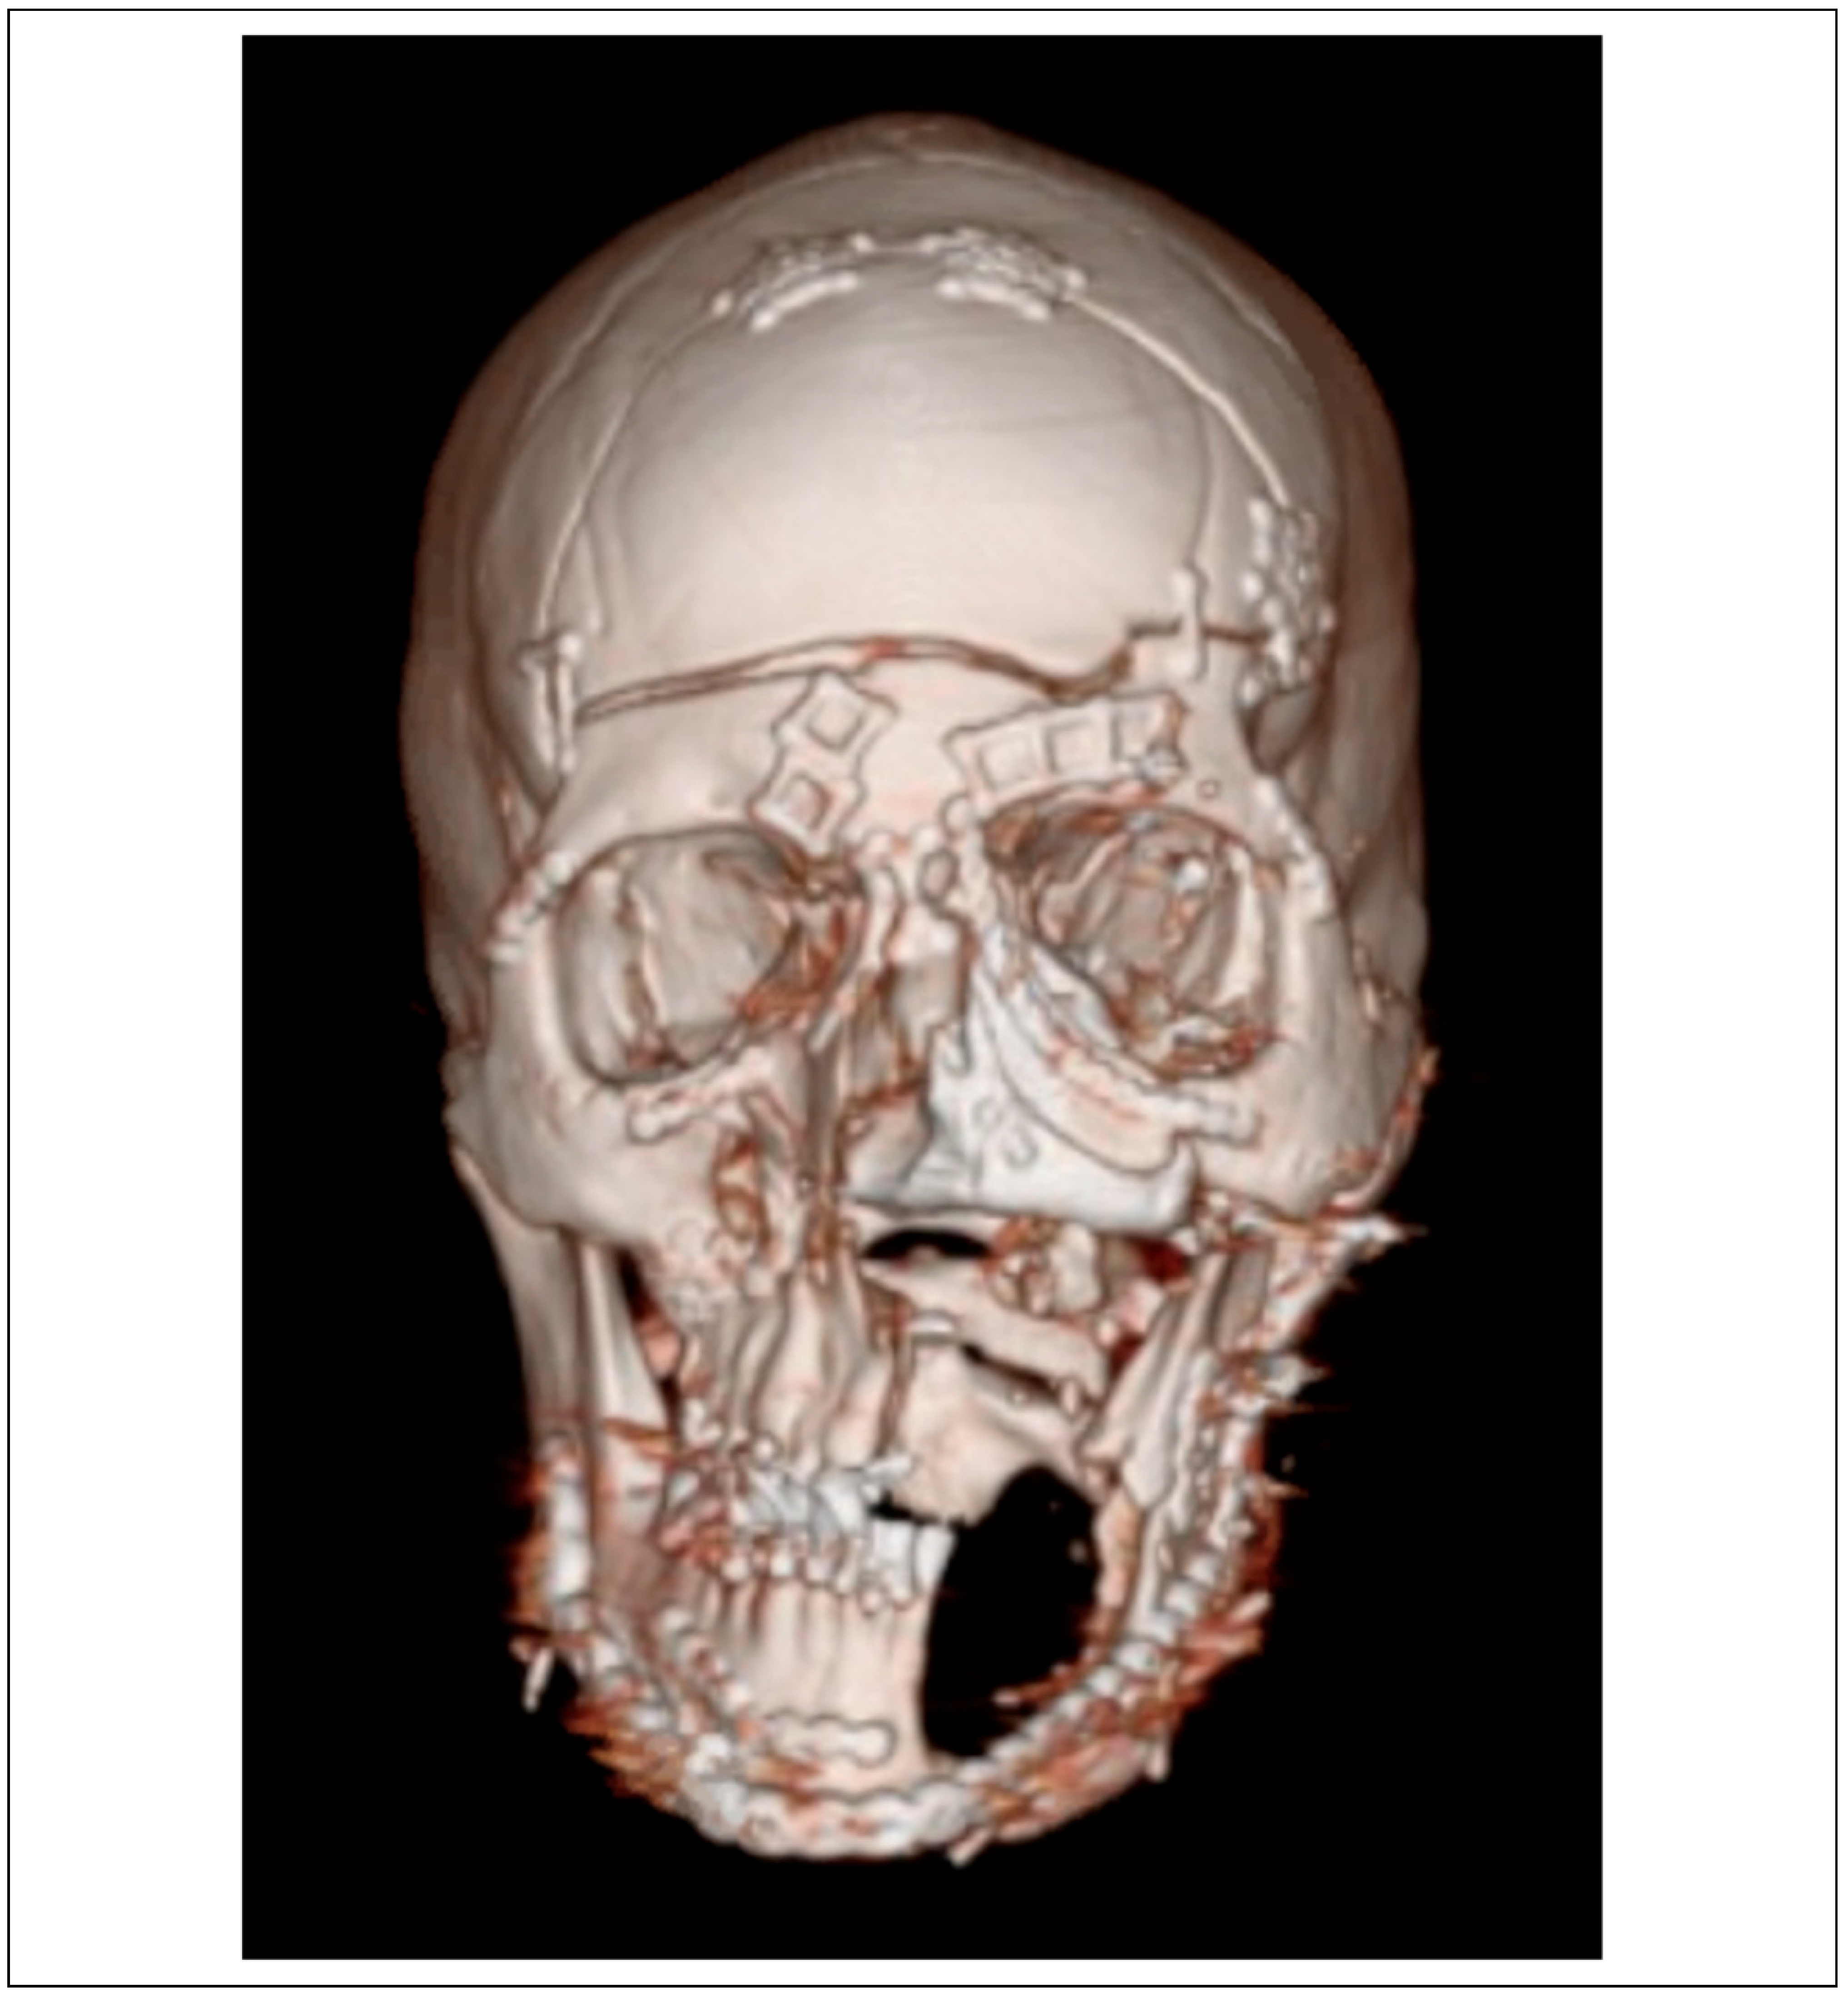

Case Series

Case Presentations